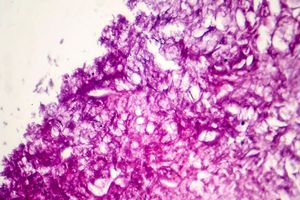

Read More[ad_1] بر اساس این تحقیق، هوش مصنوعی در تشخیص جزئیات غیرقابل مشاهده با چشم غیرمسلح، ۸۲ درصد دقیق بود، در